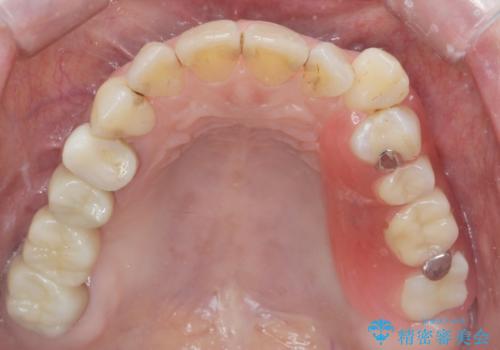

- 50代女性

- 以前から治療されている患者様です。

左上の小臼歯、大臼歯が欠損しているため。インプラントのご案内をさせてもらったところ外科的な処置は行いたくないとの事でしたので

部分入れ歯のご案内をしました。なるべく銀は見えたくないとの希望により保険の入れ歯ではなく自費の入れ歯(ノンクラスプデンチャー)を作製しました。